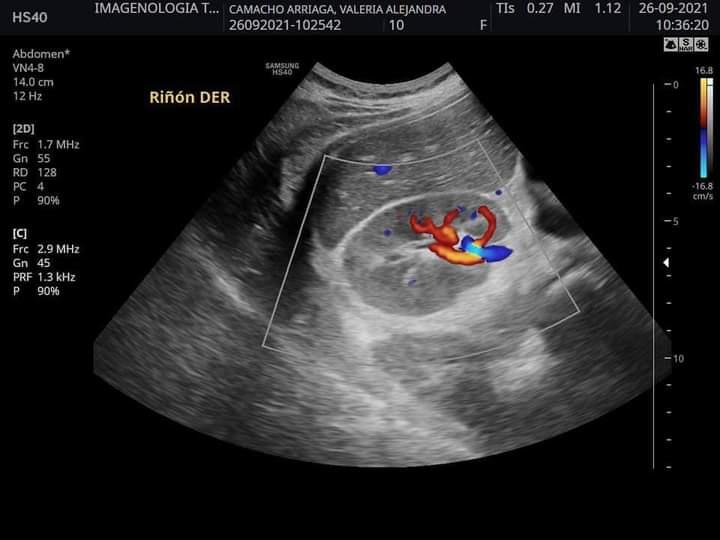

Luego de conocer la delicada situación de salud que está pasando la hija del árbitro de Ciudad Victoria, Alejandro Camacho, la cual requiere de una operación y tratamiento muy costoso al diagnosticarle Síndrome Inflamatorio Multisistémico (PIMS), la comunidad deportiva de la capital está convocando a participar en una carrera 5k en beneficio de Valeria.

Cabe descargar que la hija de Alejandro Camacho se encuentra internada en el Hospital La Salle Victoria.